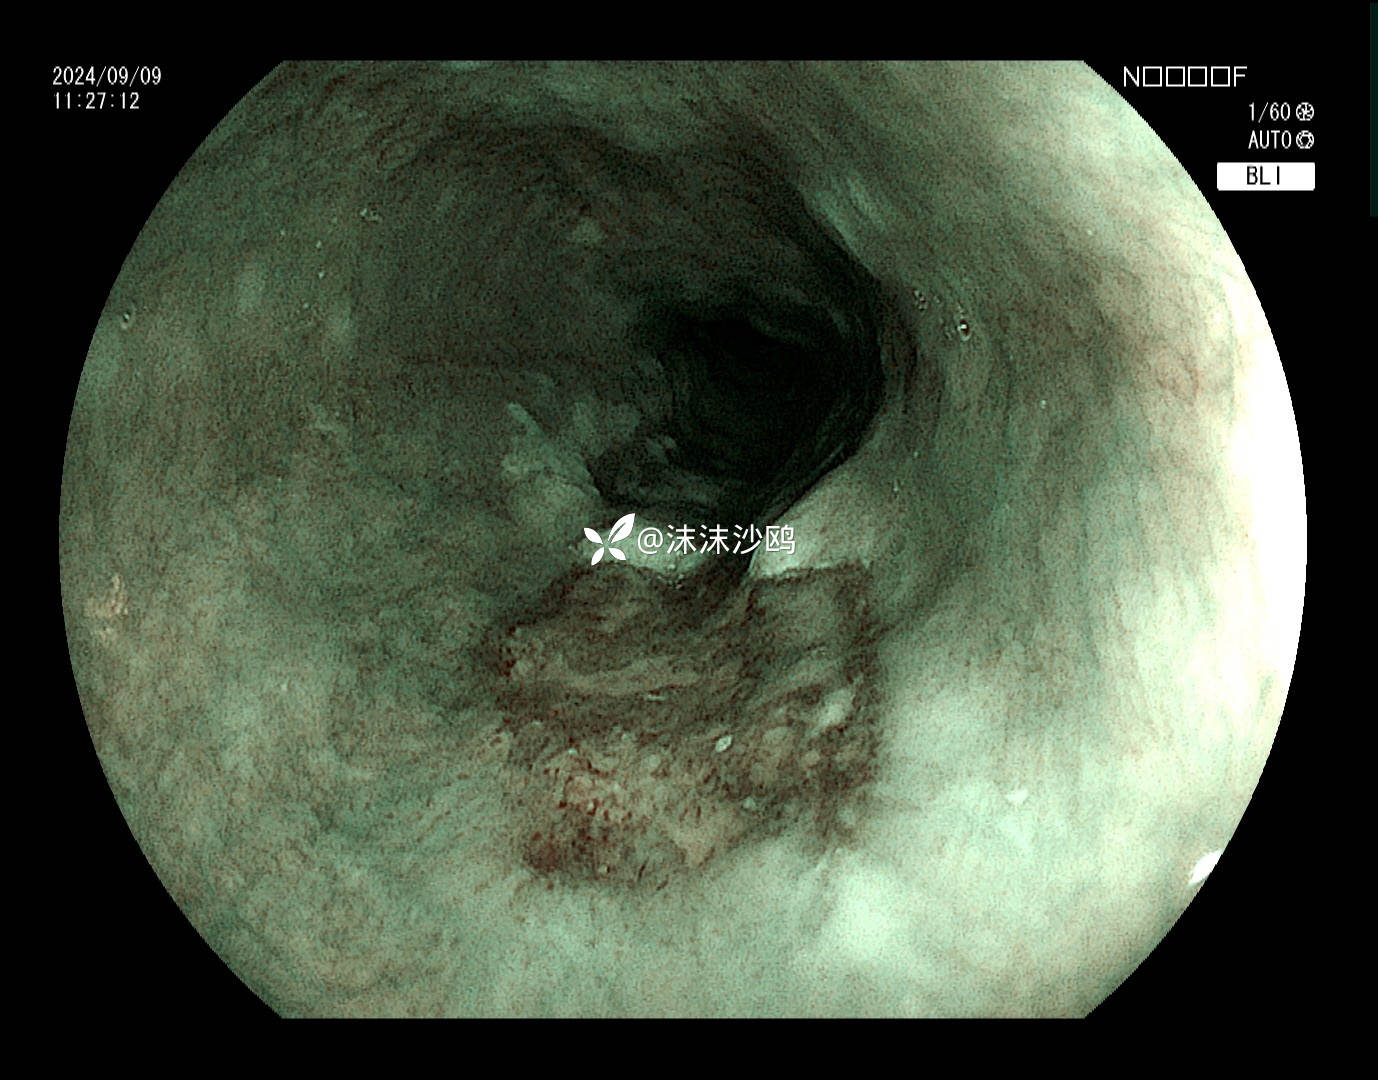

BLI

病灶肛侧

非常适合碘染的病例,可惜没有卢戈氏碘,只能电子染色放大。病灶活检2块,因出血较多,没有再继续活检。

该患者平素无明显症状,吸气注气观察病灶延展性,柔软度可,白光观察粘膜呈现发红粗糙,BLI放大观察呈现明显茶褐色,可见B1型血管,局灶可见紊乱生长的B2型血管,并见AVA区域,感觉小于0.5mm。镜下考虑浸润深度,不超过SM1,应该有内镜下D的可能性。等病理结果,希望符合内镜诊断。